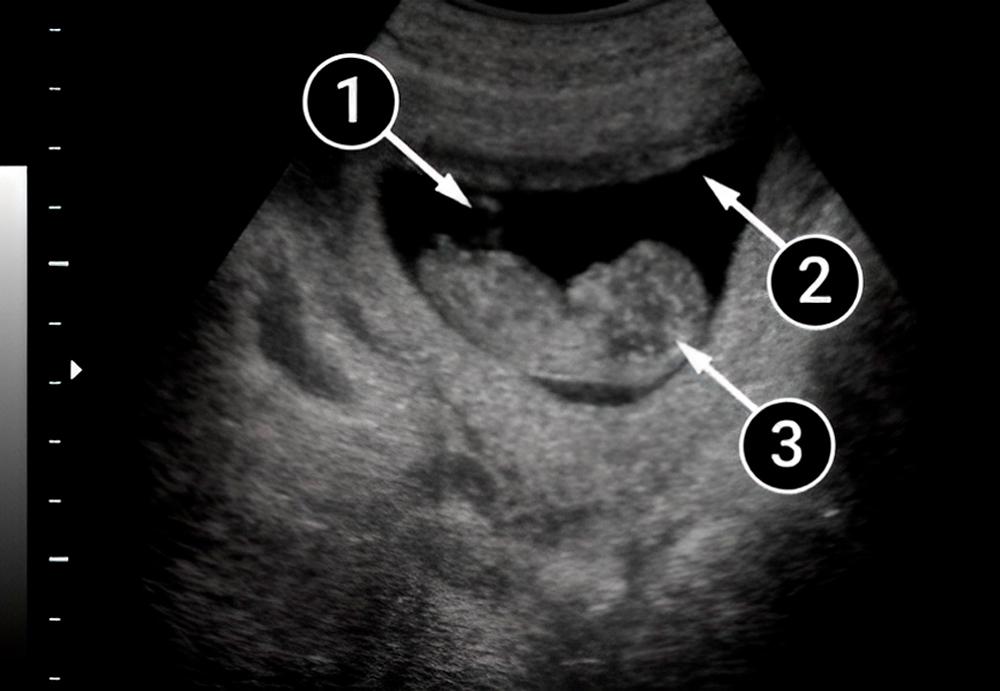

En esta imagen el bebé está flotando en el líquido amniótico y apoyado, con toda comodidad, en las paredes del saco amniótico. La imagen de perfil del bebé te brinda la oportunidad de apreciar el botón nasal y el pliegue nasal; así como las mejillas, la boca e, incluso, una pequeña oreja ubicada justo un poco por debajo de la posición habitual.

La cabeza del bebé continúa siendo muy grande, casi la mitad del tamaño del cuerpo. Pero ya está ligeramente erguida y se ve un pequeño cuello. En el área del tórax, puedes ver un punto: éste es el corazón. Las piernas no son visibles, pero se alcanza a vislumbrar el contorno de la mano derecha.

El bebé nada en el líquido amniótico, que se representa en la imagen como un gran contorno oscuro. La espiral es el cordón umbilical que proporciona una conexión estrecha entre la madre y el niño. La sangre fluye a través de sus vasos conectados con la placenta, misma que proporciona nutrición y oxígeno para su desarrollo.